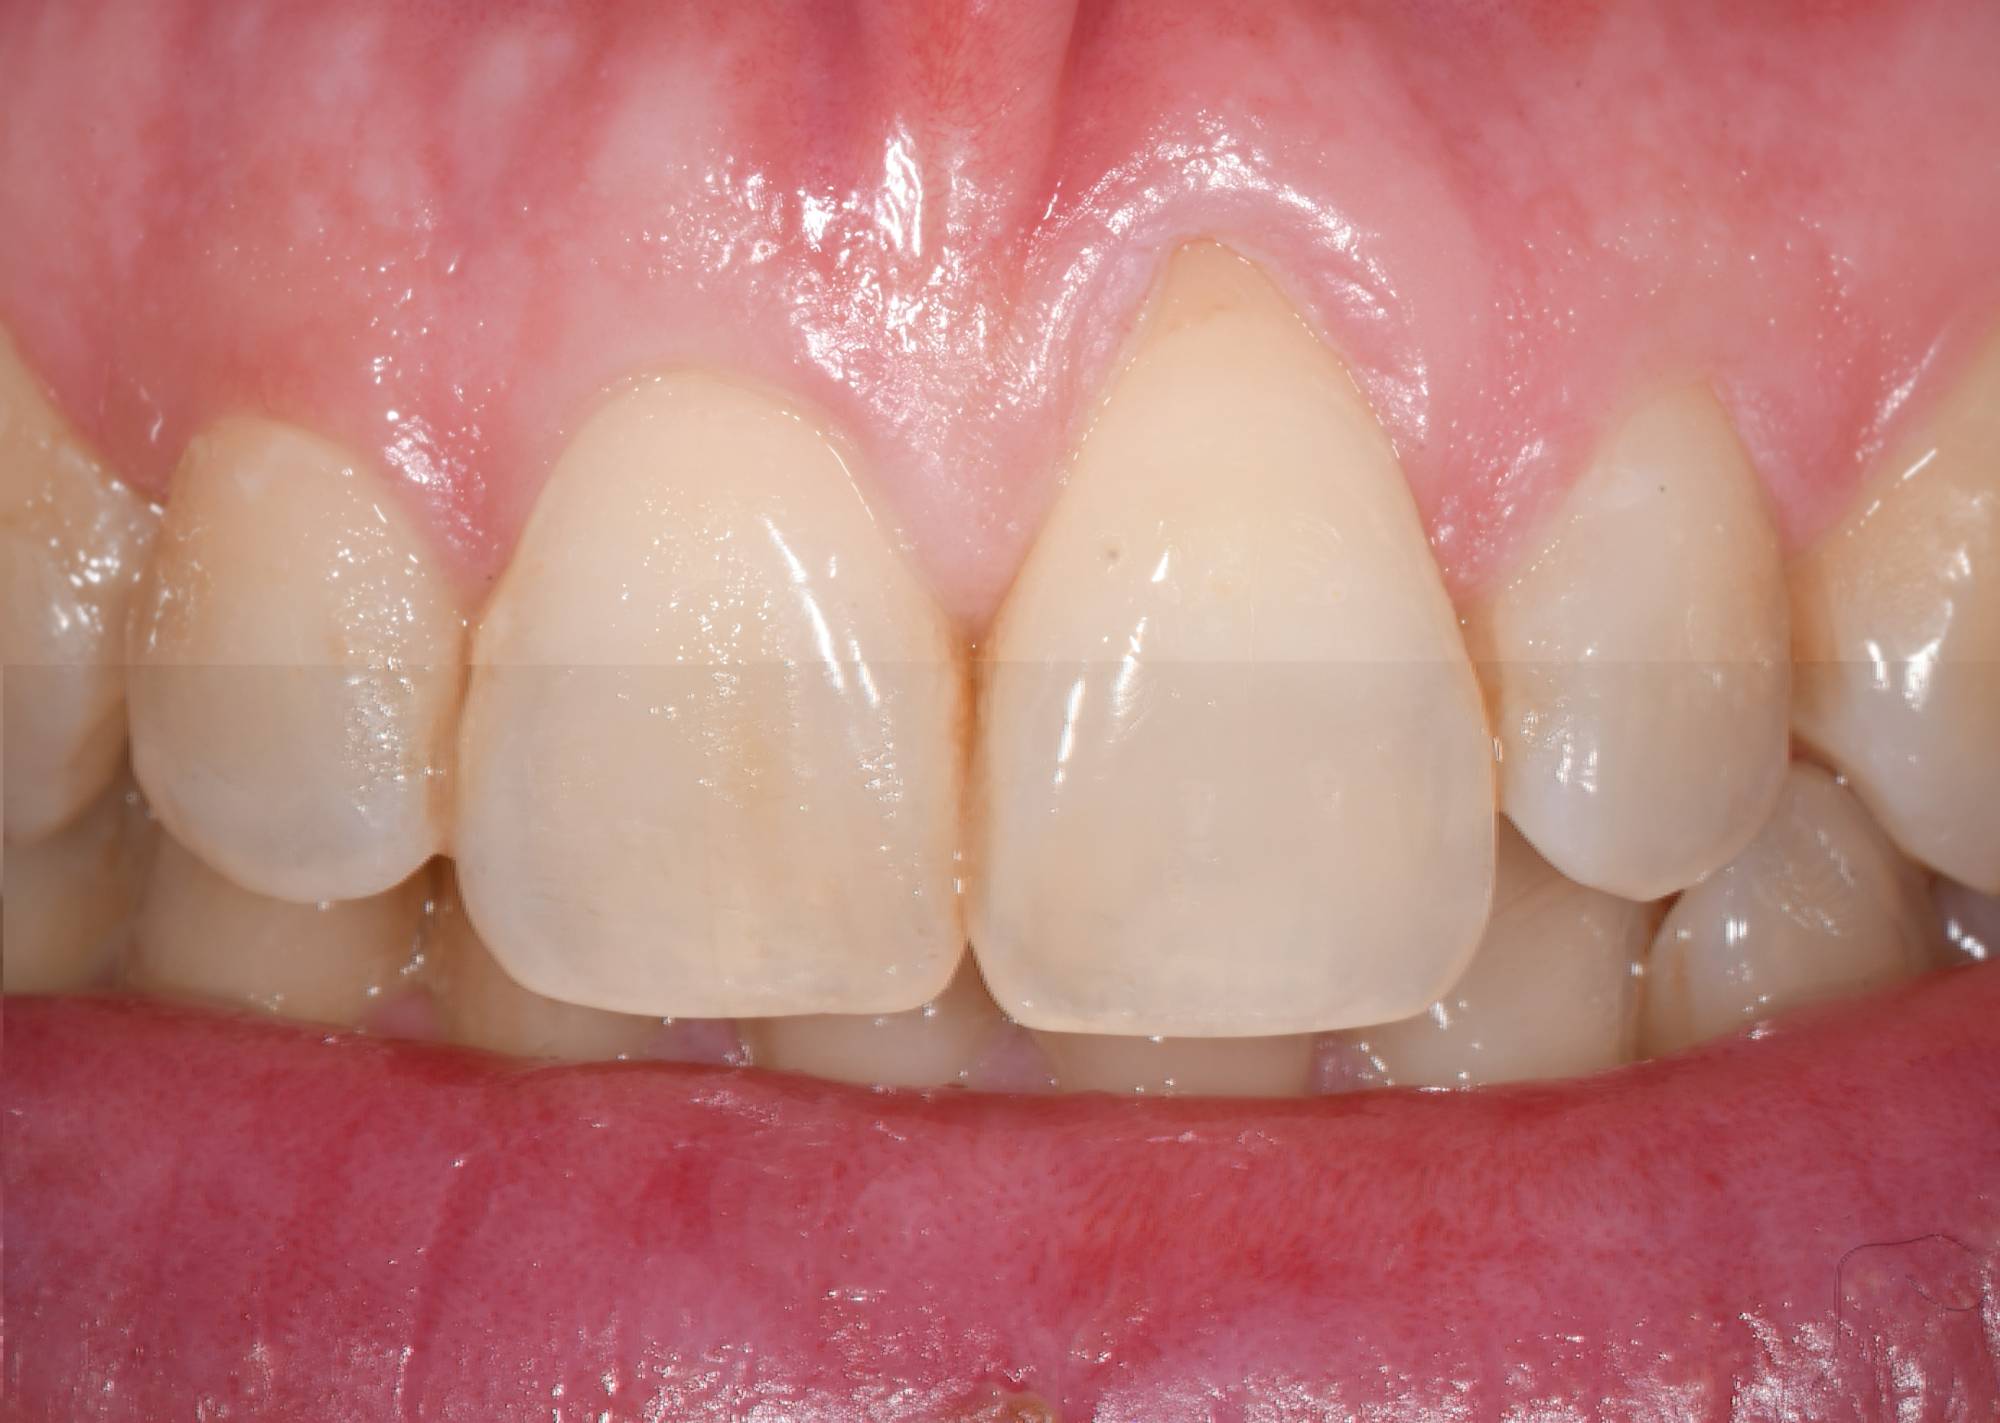

I laser sono utilizzati anche nella terapia parodontale estetica, per rimodellare i bordi gengivali e ridare una corretta proporzione tra gengiva e dente, nel cosiddetto allungamento chirurgico del dente, necessario quando un dente ha una frattura o una carie vicino alla gengiva, e infine per effettuare innesti gengivali, utilizzando porzioni di gengiva del palato per correggere recessioni gengivali significative.